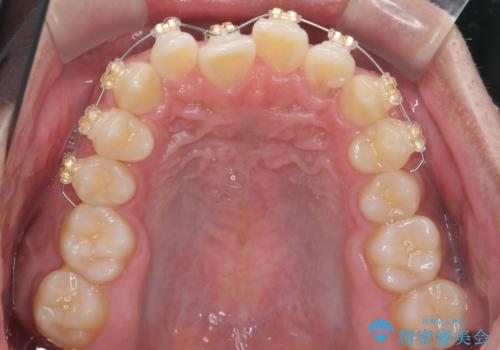

- インビザライン ワイヤー矯正

前歯を前に乗り越えさせるのは、ワイヤー矯正が一番早く歯に負担がかかりにくいです。

また、下顎はミニスクリューからマウスピースにゴムをかけて、下の歯並びが前に出ないようにして並べています。